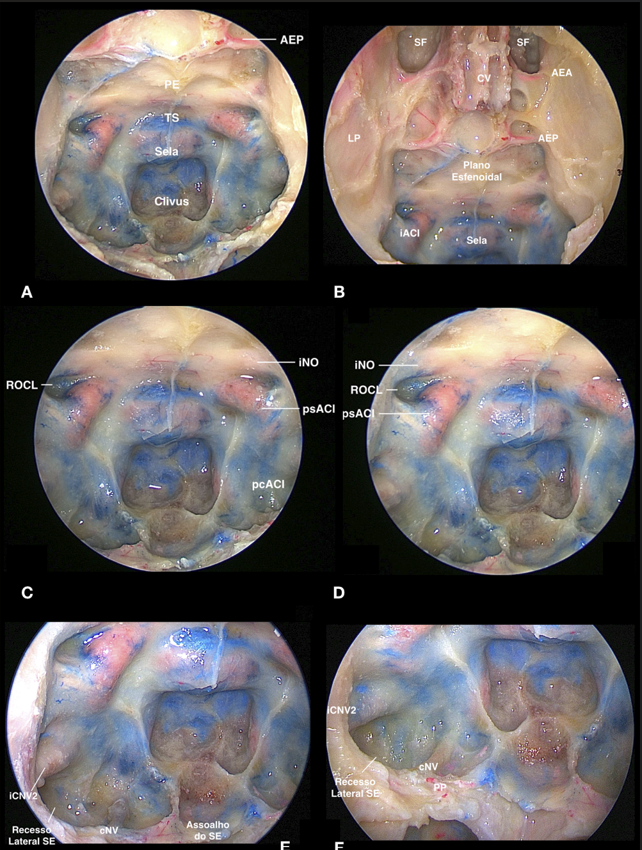

Sinta-se ao lado do professor enquanto ele realiza a dissecção completa em peças anatômicas frescas. Diferente de observar de longe em um centro cirúrgico, aqui você tem a visão privilegiada da ótica, com comentários passo a passo sobre a técnica, o manuseio dos instrumentos e os marcos de segurança.